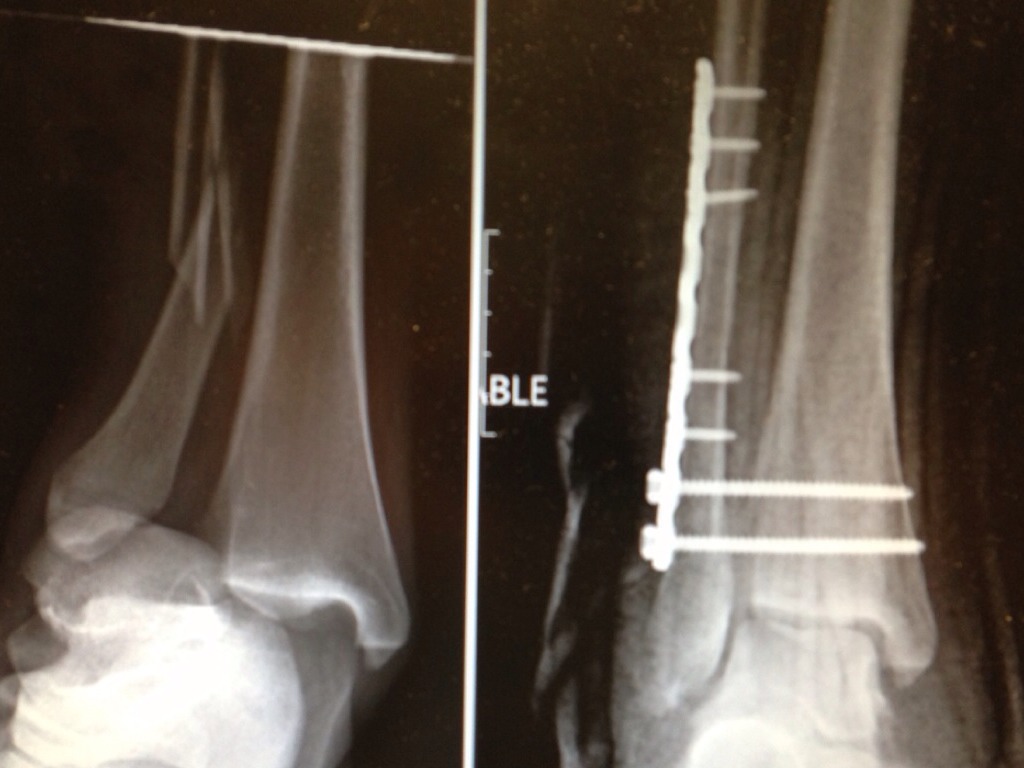

JOB DESCRIPTION

Untitled Slide